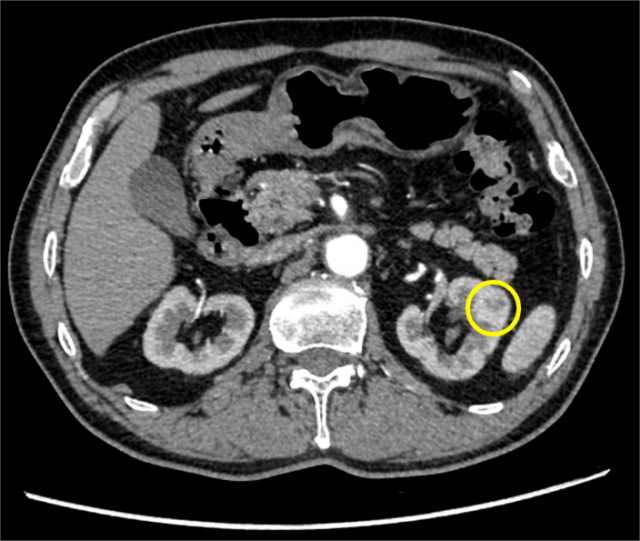

陈老伯有长达三十余年的吸烟史及十余年的老慢支病史,很担忧手术是否可以安全进行。张子臻耐心解释手术治疗的可行性和风险,并尽快为陈老伯安排了病房,同时完善全身检查。然而,在入院检查中,意外发现陈老伯的右肾中部有个直径1厘米的结节,增强CT检查高度怀疑是肾癌。

两种癌症,怎么办才好?仁济专家团队重新研讨治疗方案,以期达到最佳治疗效果。在充分评估陈老伯情况后,胃肠外科张子臻团队与泌尿科翟炜团队、麻醉科俞卫锋团队共同制定了治疗方案,决定为陈老伯进行机器人手术,一次完成胃癌和肾癌的根治性切除。